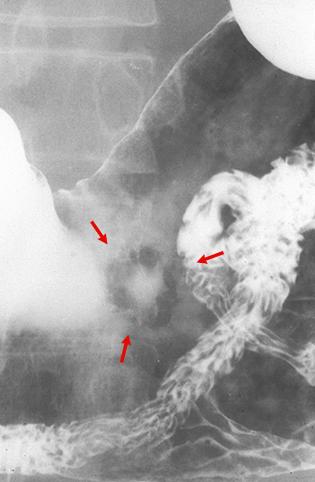

Cáncer Precoz del Estómago, tipo IIa+IIc, crecido en el tercio inferior

Tumor Epitelial Maligno/Adenocarcinoma

estómago(región)/cuerpo

Rayos X

Tipo 0(tipo superficial)/Tipo IIa(IIa+IIc)

15 - 19

sm